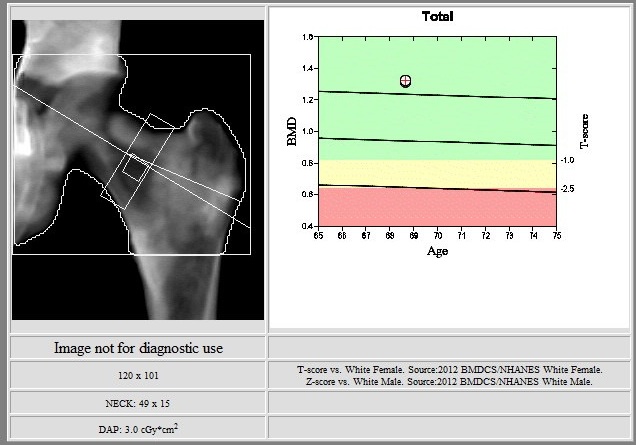

This Hologic lumbar spine DXA scan shows a black hole-type artifact over L4. Items like lead bullets and tantalum clips show up as “black”on Hologic scans. The accompanying radiograph shows the clips over L4. L4 is omitted because of overlying artifacts.

Black hole artifacts occur with dense metals such as lead and tantalum on a Hologic scan. Other metals, like stainless steel, don’t produce black hole artifacts. Presumably there is complete attenuation of both Kev peaks so the difference is zero, making the image appear black. Lead bullets are measured as having high bone mineral content (BMC) and appear black in the dual-energy mode on the Hologic scanner and blue as artifact on GE Healthcare scanners. Black hole artifacts over bone are handled differently between Hologic and General Electric. With the Hologic scanner, when a dense artifact overlies bone, the BMC associated with that artifact is excluded, but the bone area is not altered. Consequently, the bone mineral density (BMD) of the affected vertebra, and of L1-4 is decreased. The GE scanners exclude both the associated BMC and area covered by the artifact, thereby minimizing the impact on BMD. Dense artifacts in the soft tissue do not significantly affect BMD on either manufacturer’s densitometer on phantom experiments., however, further experiments need to be done to verify this finding.